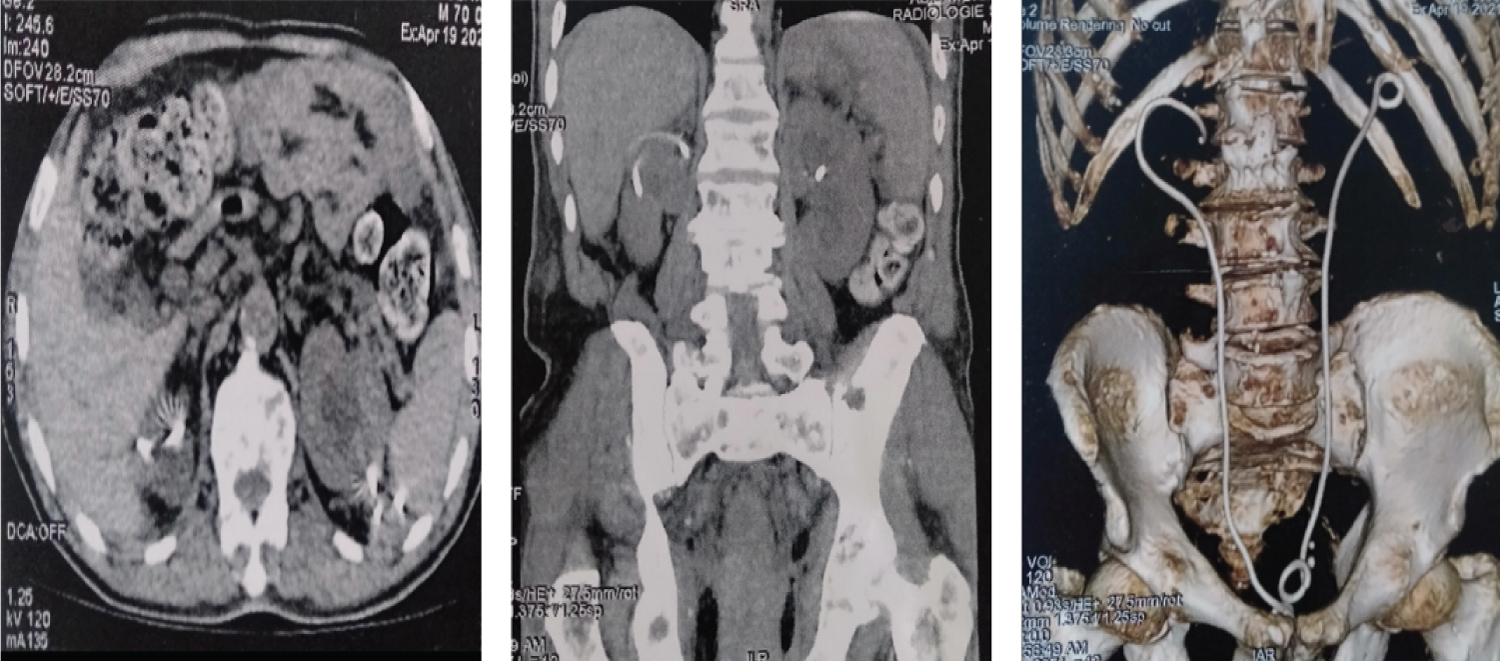

Additional scans (Figure 2) showed that both JJ probes were extra-renal, crossing the renal parenchyma and forming a subcapsular haematoma on the upper pole of the right kidney, measuring 45 × 40 mm.

Figure 2: Scans showing two JJ probes are extra-renal, perforating the renal parenchyma bilaterally, with haematoma of the upper right pole. View Figure 2